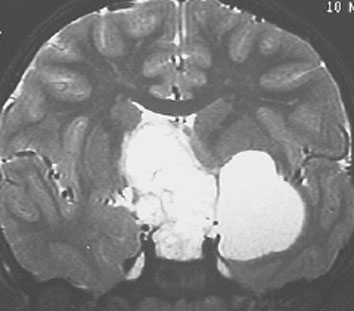

この子の症状は頭痛だけ。両親はなぜ気づかなかったのかと疑問を持ちますが,巨大になるまで症状が出ないこともあるのです。左のCTで腫瘍の周囲にバラバラと白い点状の石灰化があるので診断できます。左の視床下部から発生したクラニオでした。開頭手術しますが超高難易度です,怖いです (┯_┯) 複数回開頭手術になりましたが結果的に全摘出できています (by Dr 山本哲哉)。